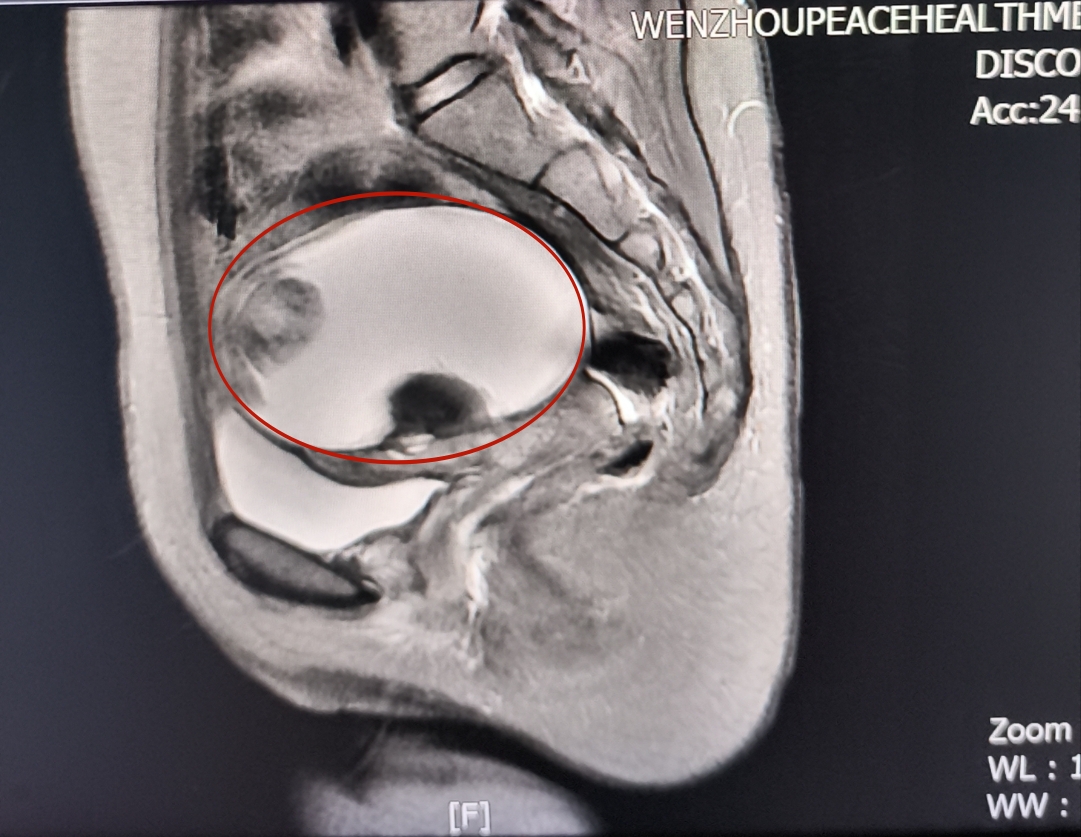

今年35歲的波蘭籍A女士人生中第一次體檢就足以讓她瞳孔地震未婚未育腹中竟然看到有怪胎...